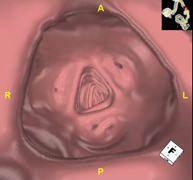

Prova diagnòstica no invasiva que consisteix en l'estudi de les artèries ilíaques i l'aorta abdominal a través de l'obtenció d'imatges d'alta definició anatòmica mitjançant l'ús d'un equip de TC (Tomografia Computeritzada) i de contrast iodat. La qualitat de les imatges permet realitzar reconstruccions en 2D i 3D gràcies a estacions de treball especialitzades en l'estudi arterial. Aquesta prova està especialment indicada com estudi prequirúrgic (mapa vascular) abans d'intervencions percutànies o quirúrgiques d'aorta abdominal, com l'estudi complementari en pacients amb isquèmia de membres inferiors, etc. - Colonoscòpia virtual

La colonoscòpia virtual és una tècnica no invasiva que permet la visualització tridimensional i bidimensional de l'intestí gros o del còlon mitjançant la presa seqüencial d'imatges captades amb TC Multidetector d'última generació. La qualitat de les imatges permet la navegació virtual per l'interior del recte i del còlon gràcies al processament en estacions de treball especialitzades. La preparació de la prova consisteix en realitzar una dieta baixa en fibra tres dies abans de la prova (per netejar el còlon i el recte) i de la ingesta de contrast oral iodat el dia abans de la prova (per marcar les femtes i poder distingir-les correctament de les possibles lesions colòniques). A diferència de la fibrocolonoscòpia, no requereix sedació ni solucions evacuants. La prova es realitza a la sala del TC, on, a través d'un petit tub flexible, s'insufla aire per distendre el còlon. - PAAF (Punció) Abdominal guiada per TC